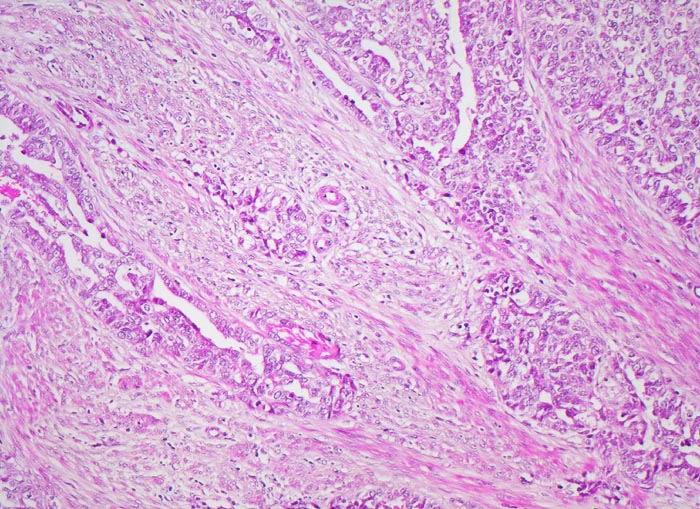

endometrioides Adenokarzinom: Invasion des Myometrium

Teils solide, teils drüsenbildende Tumorzellverbände infiltrieren die glatte Muskulatur des Myometrium.

Exophytischer, in das Uteruscavum hineinragender, weicher fokal hämorrhagischer Tumor ausgehend von der Uterushinterwand. Das Tumorgewebe infiltriert die innere Hälfte des Endometriums.

Postmenopausale Blutung. Diagnose eines endometrioiden Adenokarzinoms in der Corpuskurettage. Daraufhin Hysterektomie, Adnexektomie und Lymphadenektomie.

Die Gradierung der endometrioiden Adenokarzinome (G1 bis G3) basiert auf dem Anteil solider Tumoranteile verglichen mit dem Anteil glandulärer Tumoranteile. Wenig differenzierte Tumoren bestehen zu über 50% aus soliden Tumorarealen. Schwere Zellatypien in einem architektonisch hochdifferenzierten Tumor mit hohem glandulärem Anteil erhöhen den Tumorgrad. Wenig differenzierte Tumoren haben eine schlechtere Prognose.